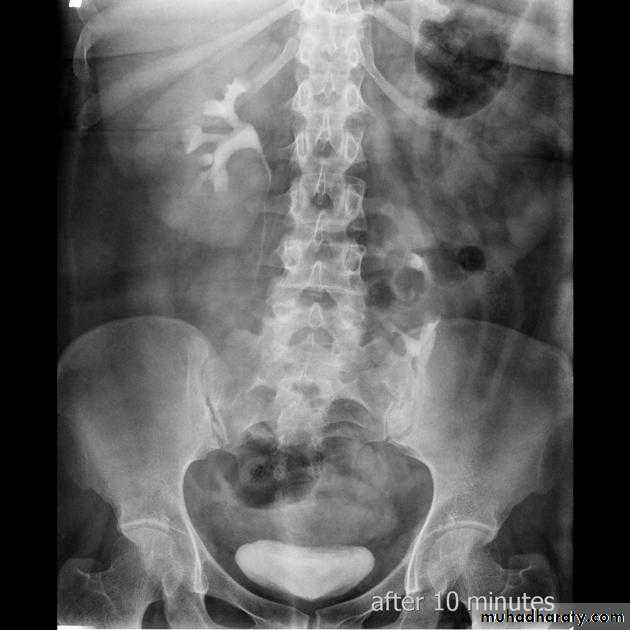

Poly cystic disease

Adult type

Present after the third decade of life , Familial.

Renal parenchyma is replaced by numerous cysts containing fluid , The cysts are of variable size ,

Clinically renal colic, loin mass , heamaturia and hypertension, Renal tissue interposed between the cysts after time dssimcted ended with renal failure

Almost bilateral.

IVU

Large kidney .

Lobulated out-line.

Distortion of pelvi- calyceal system depend on cyst size, number and position.

In advanced cases there is elongation and stretching of minor and major calyces ( spider leg).

In advanced cases IVU shows non-functioning kidney .